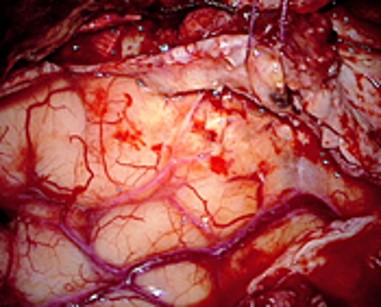

During surgery using Gleolan, the neurosurgeon views the brain through a special blue light filter on the surgical microscope.  Under this blue light, the active substance in Gleolan, aminolevulinic acid (ALA) is converted to a fluorescent compound that causes tumor cells to fluoresce a red-violet color while non-cancerous brain cells appear blue.  This procedure, known as fluorescence guided surgery, may allow the neurosurgeon to safely remove more of the tumor tissue.  Prior to Gleolan, this surgery would be performed under white light alone, making it difficult to differentiate malignant and non-malignant tissue.

Dr. Christian Ramsey of Baptist Health Lexington performed the first fluorescence-guided neurosurgery in the state last fall, using Gleolan in conjunction with blue light.  “It is great to be the first to have a technology that allows us to maximize more complete resections for these very challenging tumors,“ he says.